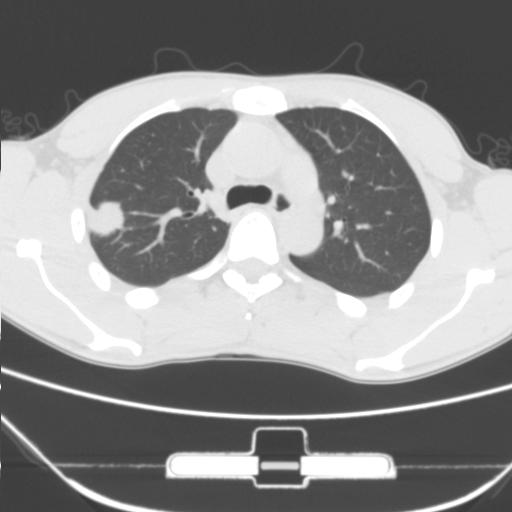

标题: CT25483:肺部病变 请指教

车祸伤者

右肺上叶后段近胸膜下结节样异常密度灶,似见分页及毛刺,考虑右肺上叶周围型肺ca,建议穿刺病理检查

缺乏病史,症状体征,但这个孤立结节具备了几乎所有的恶性征象:分叶,毛刺,空泡征,胸膜凹陷征,血管集束。

考虑右肺上叶后段周围型肺癌。